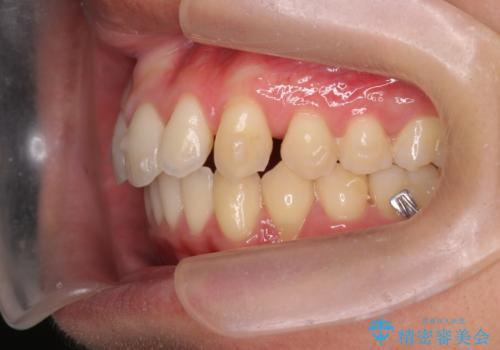

過蓋咬合・上顎前突・叢生を改善するマウスピース矯正

- 前歯のがたつき、不揃いさの改善を求めて来院されました。

・前歯の深い噛み合わせ (過蓋咬合)

・上顎前突(Angle Class2)

・叢生(がたつき)

以上のような問題点をマウスピース矯正インビザラインとマイクロインプラントを用いて矯正治療を行い改善して行きます。

20時間以上のマウスピース装着、ゴムかけを遵守していただいたおかげでしっかりと噛み合わせ、がたつきの改善を行うことができました。